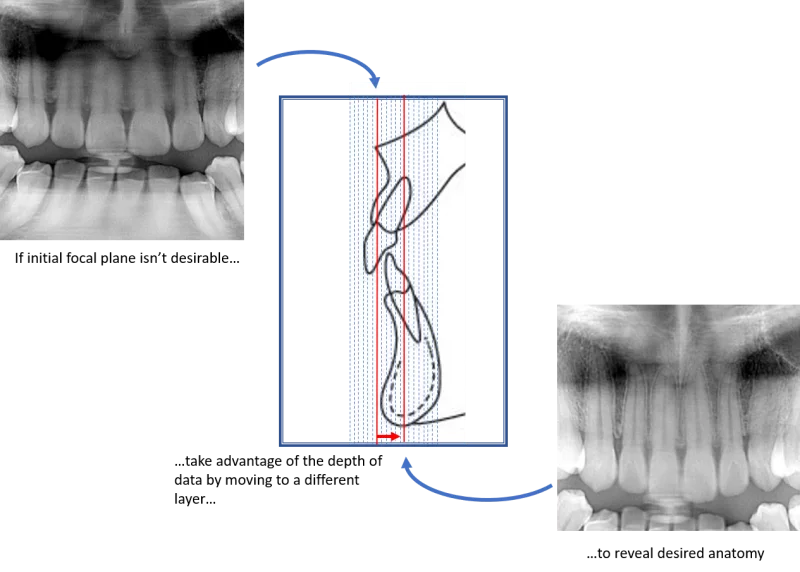

There are dental panoramic systems that are not limited to a single plane, and in fact have the ability to capture many focal troughs with one scan. These systems do this by taking many layers of varying depths in the buccal-lingual direction (some have the ability to capture over 50 layers). Typically, all this data is captured in a single scan, and then each layer is represented as a separate panoramic scan. With all this data, the user has the ability to change which panoramic they would like to see with a click of the mouse.

It’s almost like the dental professional has a stack of many panoramic x-rays with each representing a slightly different view of the anatomy – even those anterior teeth with dramatic emergence profiles.

Let’s take a look at an example.

Here is a section from a typical panoramic radiograph. In it, because of the reasons we just discussed, we can see that the image does not show the apices of the maxillary anteriors very clearly.

If this was taken with a panoramic x-ray that cannot capture multiple focal troughs, then the office is stuck with this image.

Luckily, because the panoramic x-ray performing the scan has the ability to capture many focal troughs, the operator can choose from any of the other panoramic images that were captured in that scan. Very quickly, the operator can select the image that reveals #8 and #9. This image is from the same panoramic scan as the one above. Same patient. Same scan.

However, because this patient was scanned on a panoramic x-ray than can shift the focal trough, these apices can also be revealed. Again, this is done simply by using the data captured during the original scan – no additional scans are needed. You’ll notice that in this “layer”, the crowns are less visible. This is because the maxillary anteriors have dramatic angles to the emergence profiles and therefore the crowns are in a very different layer than the apices.